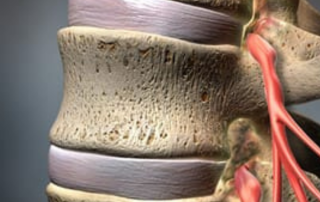

Spinal Stenoz- Omurilik Kanal Darlığı Nedir?

Kanal darlığı belirtileri ve tedavi seçenekleri. Spinal kanal darlığı, omurilik kanalının daralması sonucu sinirlerin sıkışmasıdır ve yürürken bacak ağrısıyla kendini gösterir. Spinal stenoz, omuriliğin içinden geçtiği kanalın daralması sonucu sinirlerin sıkışmasıdır. Yürüme ile artan bacak ağrısı tipiktir. Endoskopik yöntemle kanal rahatlatılabilir. Spinal stenoz, omuriliğin ve sinir köklerinin içinden geçtiği kanalın çeşitli nedenlerle daralması sonucu sinir dokusunun sıkışmasıdır. En sık bel bölgesinde görülür ve çoğu zaman “bel fıtığı gibi” başlayıp farklı bir tabloya evrilir: Problem tek bir disk parçasından çok, kanalın genel olarak daralmasıdır. Bu daralma sinirlerin hareket alanını kısıtladığında, özellikle yürüyüşle belirginleşen şikâyetler ortaya çıkar. Kanal darlığı belirtileri nelerdir? Spinal [...]